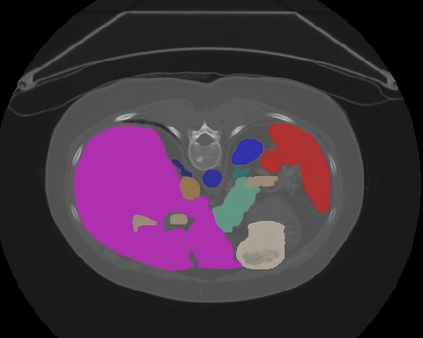

Transformers, the default model of choices in natural language processing, have drawn scant attention from the medical imaging community. Given the ability to exploit long-term dependencies, transformers are promising to help atypical convolutional neural networks (convnets) to overcome its inherent shortcomings of spatial inductive bias. However, most of recently proposed transformer-based segmentation approaches simply treated transformers as assisted modules to help encode global context into convolutional representations without investigating how to optimally combine self-attention (i.e., the core of transformers) with convolution. To address this issue, in this paper, we introduce nnFormer (i.e., Not-aNother transFormer), a powerful segmentation model with an interleaved architecture based on empirical combination of self-attention and convolution. In practice, nnFormer learns volumetric representations from 3D local volumes. Compared to the naive voxel-level self-attention implementation, such volume-based operations help to reduce the computational complexity by approximate 98% and 99.5% on Synapse and ACDC datasets, respectively. In comparison to prior-art network configurations, nnFormer achieves tremendous improvements over previous transformer-based methods on two commonly used datasets Synapse and ACDC. For instance, nnFormer outperforms Swin-UNet by over 7 percents on Synapse. Even when compared to nnUNet, currently the best performing fully-convolutional medical segmentation network, nnFormer still provides slightly better performance on Synapse and ACDC.